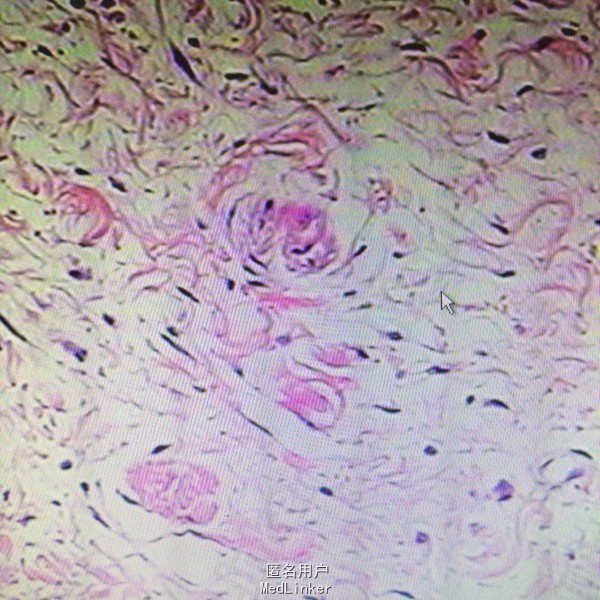

诊断:脑脊膜膨出 处理:枕部脑膜膨出囊切除术➕硬脑膜修补术

随访:病情缓解出院 讨论:脑脊膜膨出多为先天性疾病,该患儿7个月发病,脑组织从颅骨缺损口向外膨出犹如蕈状,故又有脑蕈之称(BrainFungus)。男性好发颅前部脑膨出,女性多见颅后部脑膨出,约占70%。神经系统症状轻者无明显神经系统症状,重者与发生的部位及受损的程度有关,可表现智力低下,抽搐及不同程度的瘫痪,腱反射亢进,不恒定的病理反射。